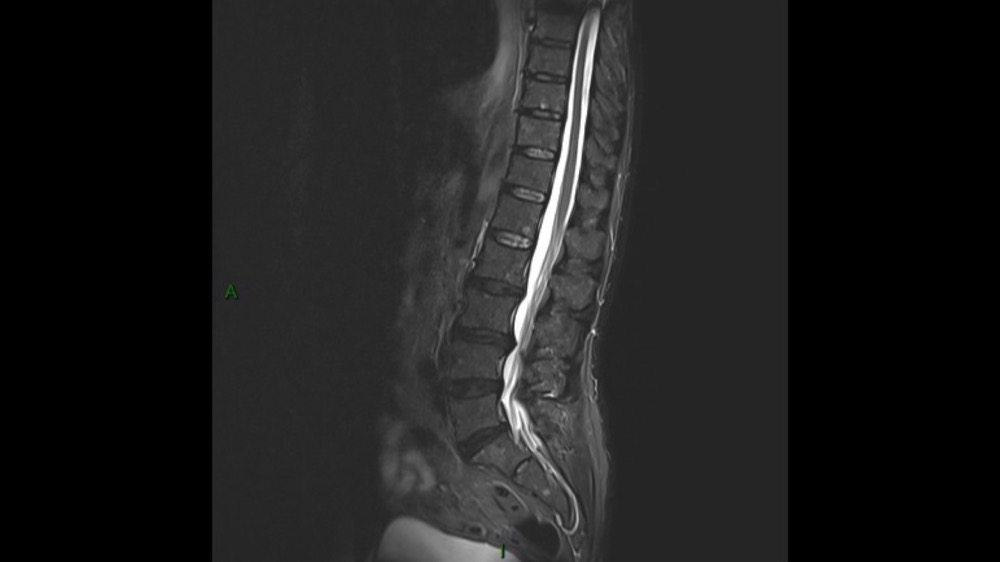

Lombo-cruralgie subaiguë trompeuse

Pascalie Jallerat 22/06/2020